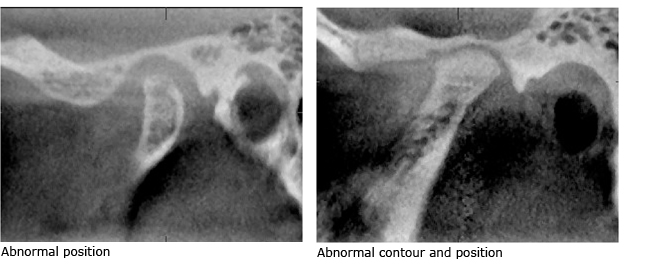

Image Comparison of MRI Normal/Abnormal Disc Position